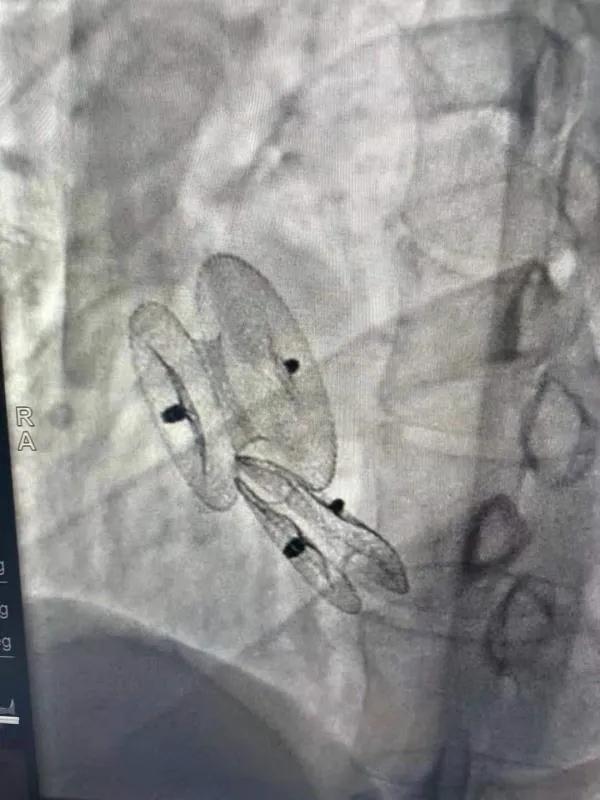

先天性心臟病房間隔缺損呈多孔型怎么辦?患者并非只能選擇開胸手術(shù)。近日,西安國際醫(yī)學(xué)中心醫(yī)院心臟病醫(yī)院成功開展一例雙孔房間隔缺損雙傘介入封堵術(shù)。

房間隔缺損是先天性心臟病的一種,介入手術(shù)相較于傳統(tǒng)的外科手術(shù)損傷小,風(fēng)險相對較低,術(shù)后恢復(fù)快。一般的房間隔缺損多呈單孔,封堵難度較小,而雙孔房間隔的封堵難度大大增加,至今僅有國內(nèi)頂尖的封堵專家成功完成了數(shù)例而已。

患者是位27歲的年輕女性,經(jīng)常感到心慌,心臟超聲發(fā)現(xiàn)房間隔缺損,并且房間隔缺損呈雙孔型,大的約14mm,小的約9mm,兩個缺損間相隔較遠(yuǎn),介入封堵難度非常大。

在詳細(xì)了解患者病情,仔細(xì)閱讀患者影像資料后,曾廣偉主任已經(jīng)有了清晰的手術(shù)策略。在精心的準(zhǔn)備和團(tuán)隊的配合下,曾主任順利的利用兩個封堵器對房缺進(jìn)行了封堵。